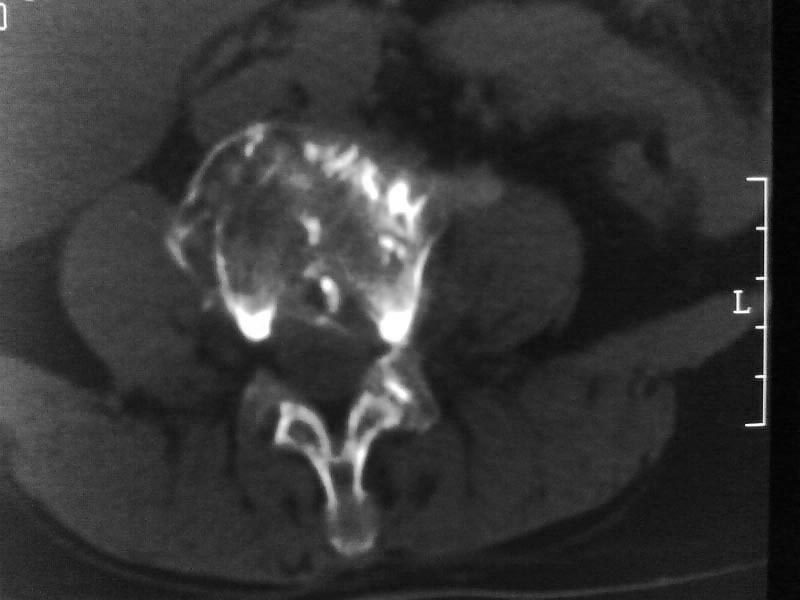

定位相示l2呈楔形改变(ct示陈旧性骨折改变,图像未传),l4.5椎体融合,以下是l4.5ct平扫.请各位看看,

考虑结核(有破坏、硬化及死骨)。

1、三四椎体结核,2、水平骶椎。

1、l1压缩性骨折(陈旧性)。

2、l3、4椎体结核。

就是腰1压缩性骨折,腰3\\4椎体结核(融合),水平骶椎.

支持 l1椎体陈旧性压缩性骨折;l3、4椎体结核(融合);水平骶椎。